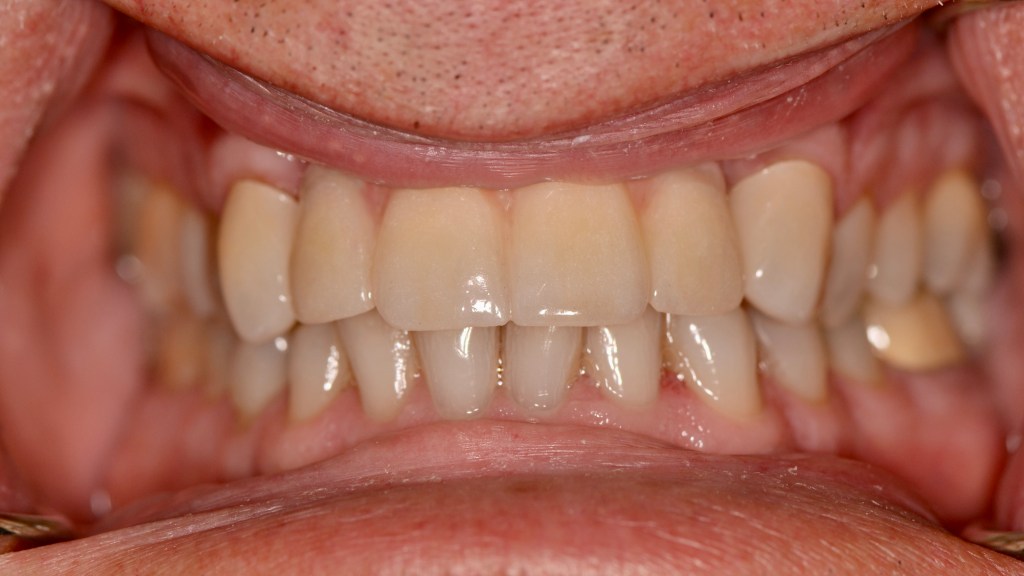

Implant Bridge and Ceramic Crowns